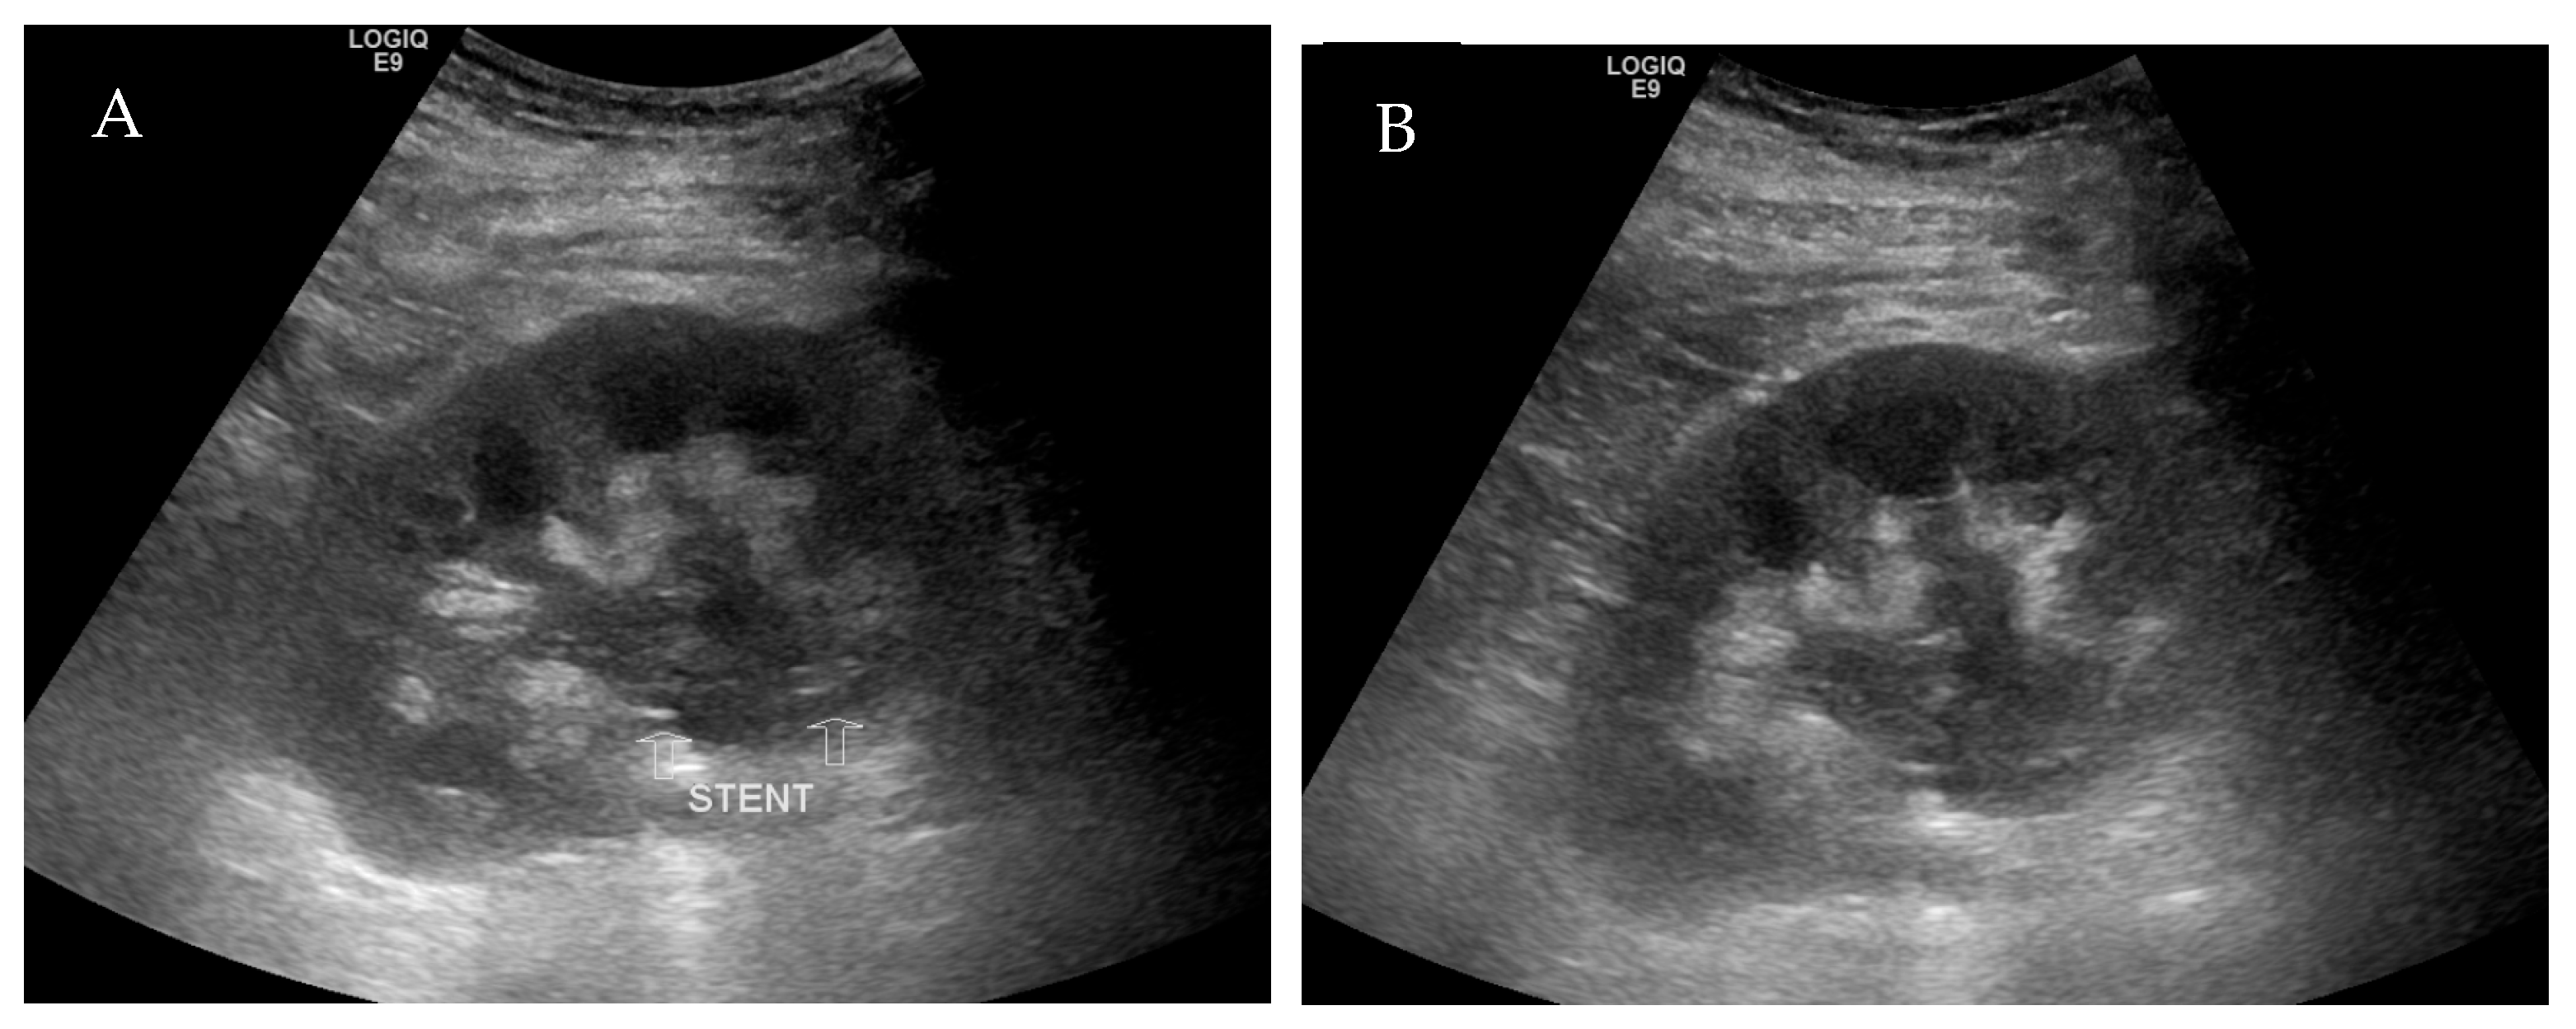

The CT scan without contrast was repeated on post-operative day 6, which demonstrated dense dilatation of the renal collecting system and appropriate positioning of the ureteral stent (Figure 2). His urine output subsequently decreased—producing approximately 150 mL in 24 h. A repeat ultrasound demonstrated a dilated renal pelvicalyceal system containing echogenic debris (Figure 3), so the decision was made to remove the ureteral stent due to likely occlusion on post-operative day 8. Upon manipulation and removal of the stent, a large amount of old blood sediment immediately drained from the ureteral orifice. Urine output improved significantly after stent removal with resolution of hematuria. On post-operative day 10, renal function continued to improve: creatinine 4.3 mg/dL and eGFR 15 mL/min/1.73 m2. He was discharged and scheduled for close outpatient follow-up.

Figure 3. Transplant kidney ultrasound demonstrated the proximal end of the ureteral stent within the renal pelvis (A) and persistently dilated renal pelvicalyceal system containing echogenic debris (A,B).